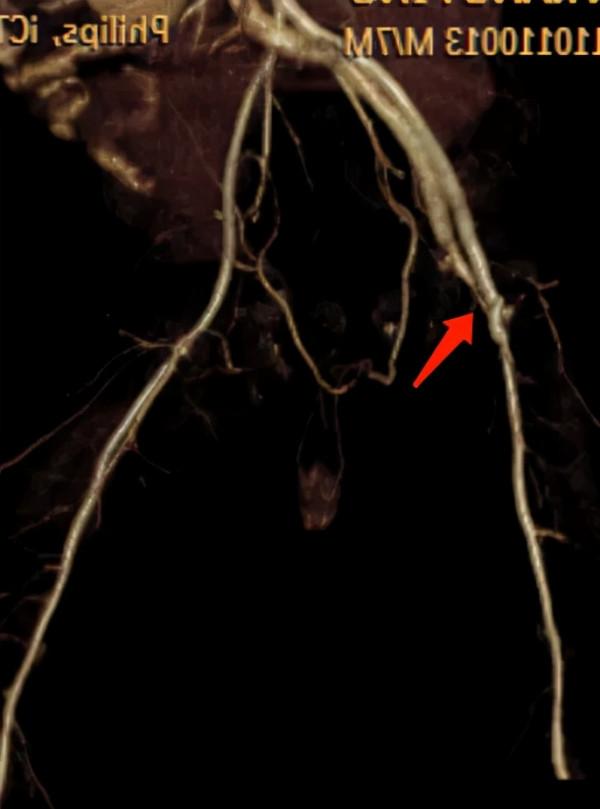

完善下肢血管的彩超檢查後,康康大腿根部的病變引起醫生注意——有一根動脈血管與附近的靜脈血管“相通了”,醫學術語叫“股動靜脈瘻”。

動靜脈連通的位置

丁語一邊安慰家長,一邊為康康安排進一步的CT血管造影檢查。明確了瘻口的數目和位置後,她建議康康採用“複合血管手術”。